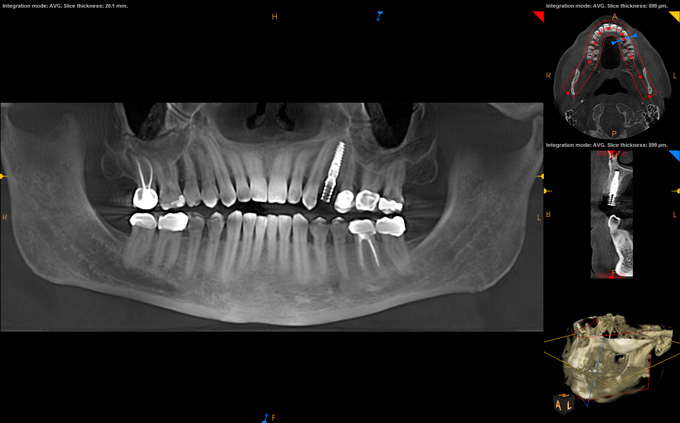

(7.) Postoperative CBCT images confirming implant placement according to the digital plan.

Figure 7

(8.) Postoperative CBCT images confirming implant placement according to the digital plan.

Figure 8

(9.) Virtual plan showing that the extraction of tooth No. 20 followed by robot-assisted immediate implant placement at the sites of teeth Nos. 19 and 21 was a viable option.

Figure 9

(10.) Crown location at site No. 19 optimized on the virtual plan.

Figure 10

(11.) Implant position at site No. 21 optimized on the virtual plan.

Figure 11

(12.) Postoperative CBCT image of actual implant placement at site No. 21.

Figure 12

(13.) Postoperative CBCT image of actual implant placement at site No. 19.

Figure 13

After a CBCT scan (Figure 3) and a digital impression were obtained for diagnosis and treatment planning, the DICOM file from the CBCT scan and the STL file from the digital impression were merged in a treatment planning software application for evaluation. A virtual crown was then created to facilitate a restoration-driven approach. The vital structures and osseous anatomy were identified, and the implant position was planned virtually (Figure 4 and Figure 5).

On the day of surgery, a prefabricated tooth-borne splint with an extraoral extension was placed on the patient's contralateral arch and secured with a cold-cure hard relining material. The splint was uniquely designed so that a "breakaway" technique could be used to remove it upon completion of the case. Next, a resin attachment with seven round metal beads, called a fiducial array, was magnetically attached to the splint extension (Figure 6). A new CBCT scan was then taken to capture the fiducial array and relate the splint to the patient's anatomy. After a calibration process was completed to ensure the accuracy of the robotic guidance arm, it was attached to the oral splint and secured. The guidance arm allows the system to identify the patient's anatomy, detect movement, and move with the patient. Profound anesthesia was achieved, and tooth No. 12 was extracted utilizing an atraumatic flapless technique. Next, an implant bur was placed into the robotic handpiece and measured, and accuracy was again confirmed using a predetermined landmark on tooth No. 11. The implant drilling protocol was then completed using the robotic handpiece. Drilling angle, position, and depth are constrained to the plan by the robotic arm, which uses haptic guidance to limit the movement of the handpiece to the proper position by providing physical resistance and feedback during the drilling process. The monitor provides visual navigation and confirmation of the correct angle, position, and depth; however, the surgeon may complete the drilling protocol by viewing either the monitor or the patient directly. After the same robotic protocol was used to place the implant into the osteotomy, allogenic bone was injected and condensed into the osseous defect and a temporary cylinder was placed in preparation for an immediate nonloaded provisional crown. A postoperative CBCT scan confirmed that the dental implant had been placed in accordance with the virtual plan (Figure 7 and Figure 8).

A healthy 60-year-old female presented for an emergency evaluation because she was experiencing pain associated with tooth No. 20. It was mobile, malposed, and given a diagnosis of irreversible pulpitis. In addition, teeth Nos. 19 and 21 had been missing for more than 5 years. After the evaluation, a discussion revealed that the patient desired implant reconstruction of the lower left quadrant. During this initial visit, a CBCT scan was obtained, and the virtual restoration-driven implant planning was completed, confirming that extraction of tooth No. 20 with robot-assisted immediate implant placement at the sites of teeth Nos. 19 and 21 was a viable option (Figure 9 through Figure 13). Splint placement, CBCT capture of the fiducial array, calibration, and landmark confirmation were completed as described in the first case report. Following the administration of intravenous sedation and local anesthesia, tooth No. 20 was atraumatically extracted. Flap access was obtained from the site of tooth No. 18 to the site of tooth No. 22, and robot-assisted surgical implant placement was completed at the sites of teeth Nos. 19 and 21. Intraoperatively, guide pins were placed to evaluate the position of the proposed osteotomies, and it was determined that both implants should be tilted buccally by 0.4 mm. The necessary changes were made in the software application, and the new implant placement plan was immediately ready for robotic implementation. The implants were robotically delivered to their planned positions at the sites of teeth Nos. 19 and 21 and torqued to initial stability at 50 Ncm and 45 Ncm, respectively (Figure 14 and Figure 15). Healing abutments were placed, and the tissue was closed primarily. In this case, robotic assistance facilitated the performance of surgery on the same day that the patient initially presented and permitted intraoperative modifications to be made.